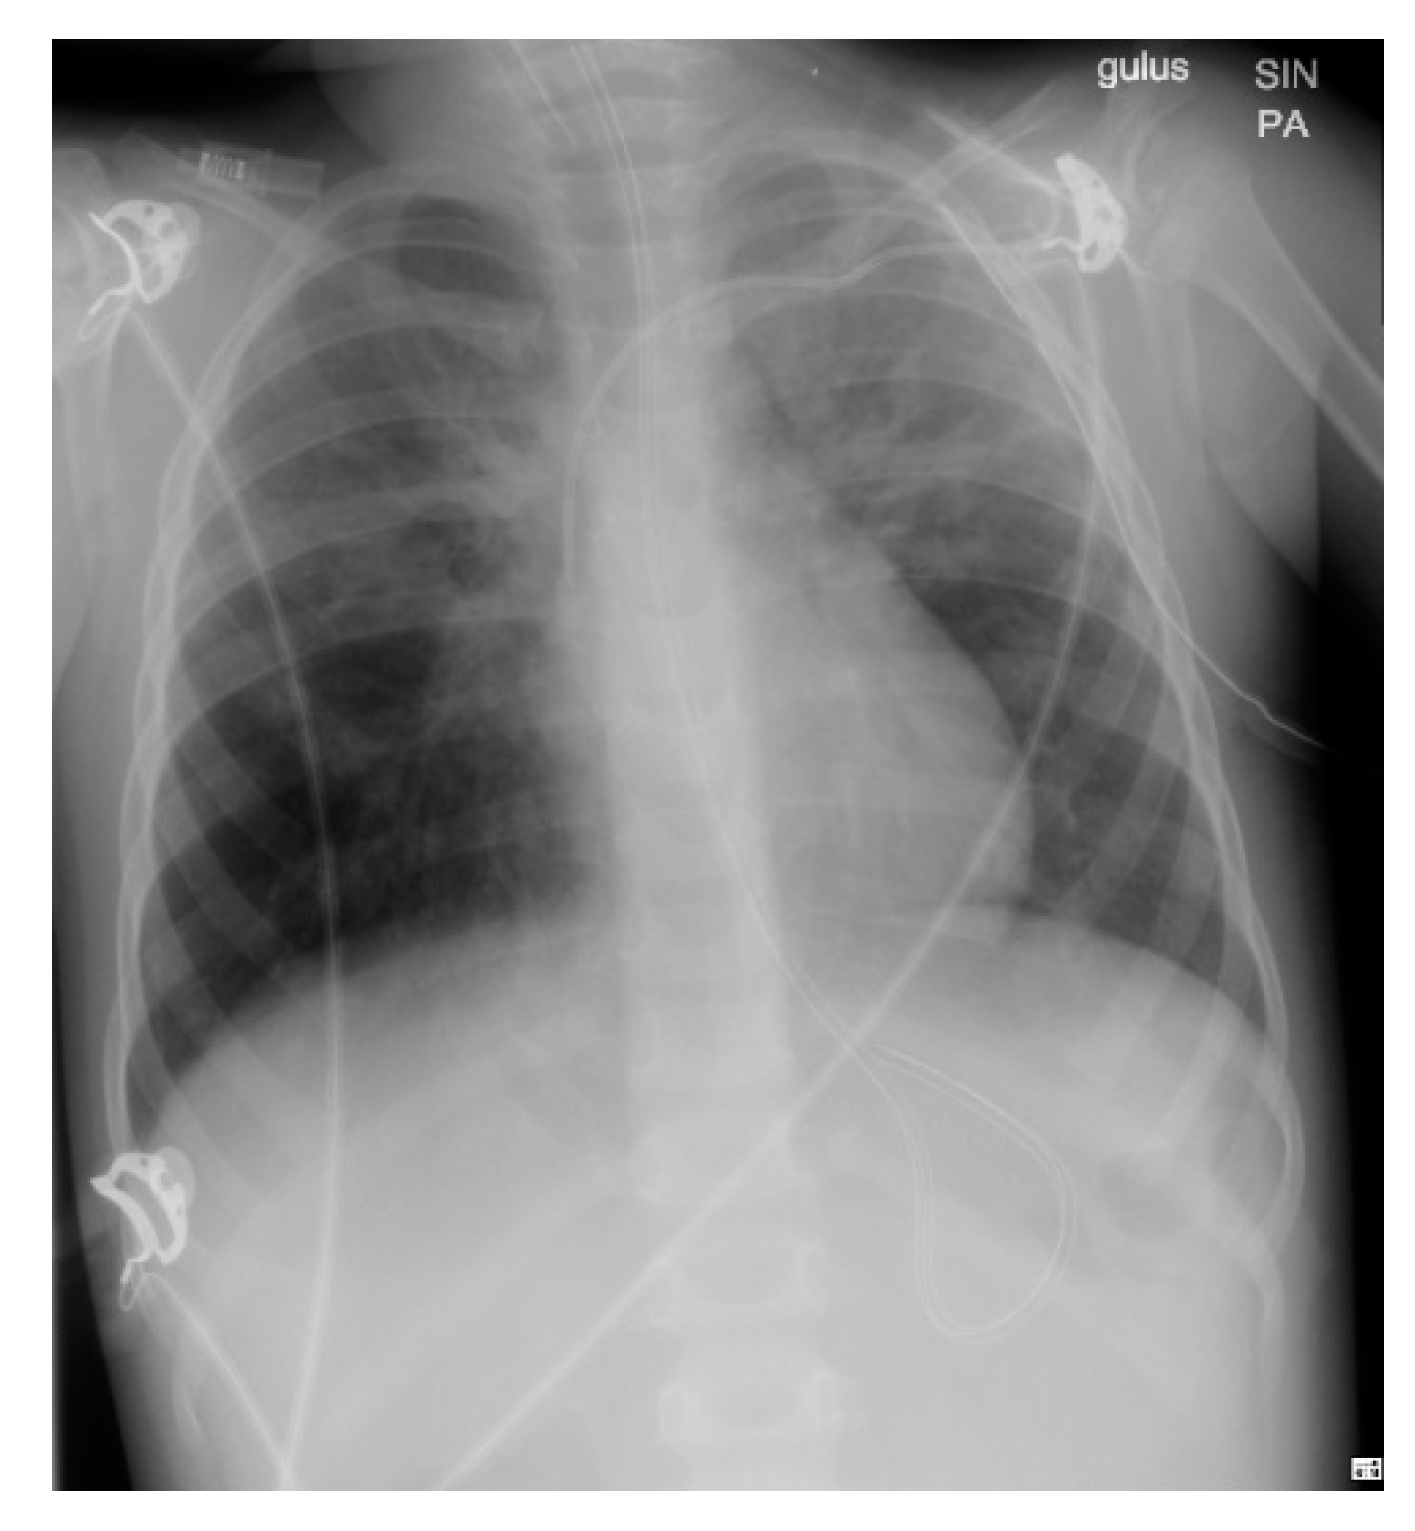

A rapid antigen test performed on admission was SARS-CoV-2 positive. This was confirmed with PCR testing and led to a diagnosis of COVID-19. Over the following four days, the patient’s condition worsened with increasing fatigue, cough, abdominal pain, and tachypnea (reaching 100/min), dropping SpO2 (87–90% on room air). A chest X-ray obtained on day 2 (Figure 1) revealed multiple infiltrates present bilaterally, more pronounced on the left lung than the right, consistent with bilateral pneumonia and a capillary blood gas (CBG) test revealed type I respiratory failure (RF).

Figure 1. Day 2 Chest X-ray demonstrating bilateral pneumonia.